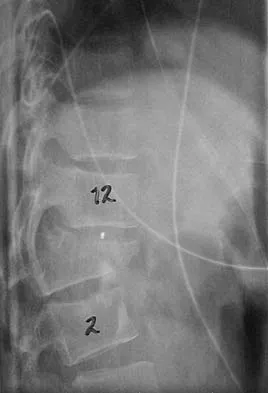

Question 7

Figures 21a and 21b show the radiographs of a 22-year-old man who was shot through the abdomen the previous evening. An exploratory laparotomy performed at the time of admission revealed a colon injury. Current examination reveals no neurologic deficits. Management for the spinal injury should include

Explanation